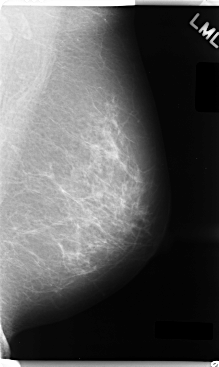

C_0035_1.LEFT_MLO

LEFT_MLO LINES 4760 PIXELS_PER_LINE 2840 BITS_PER_PIXEL 12 RESOLUTION 50 NON_OVERLAY